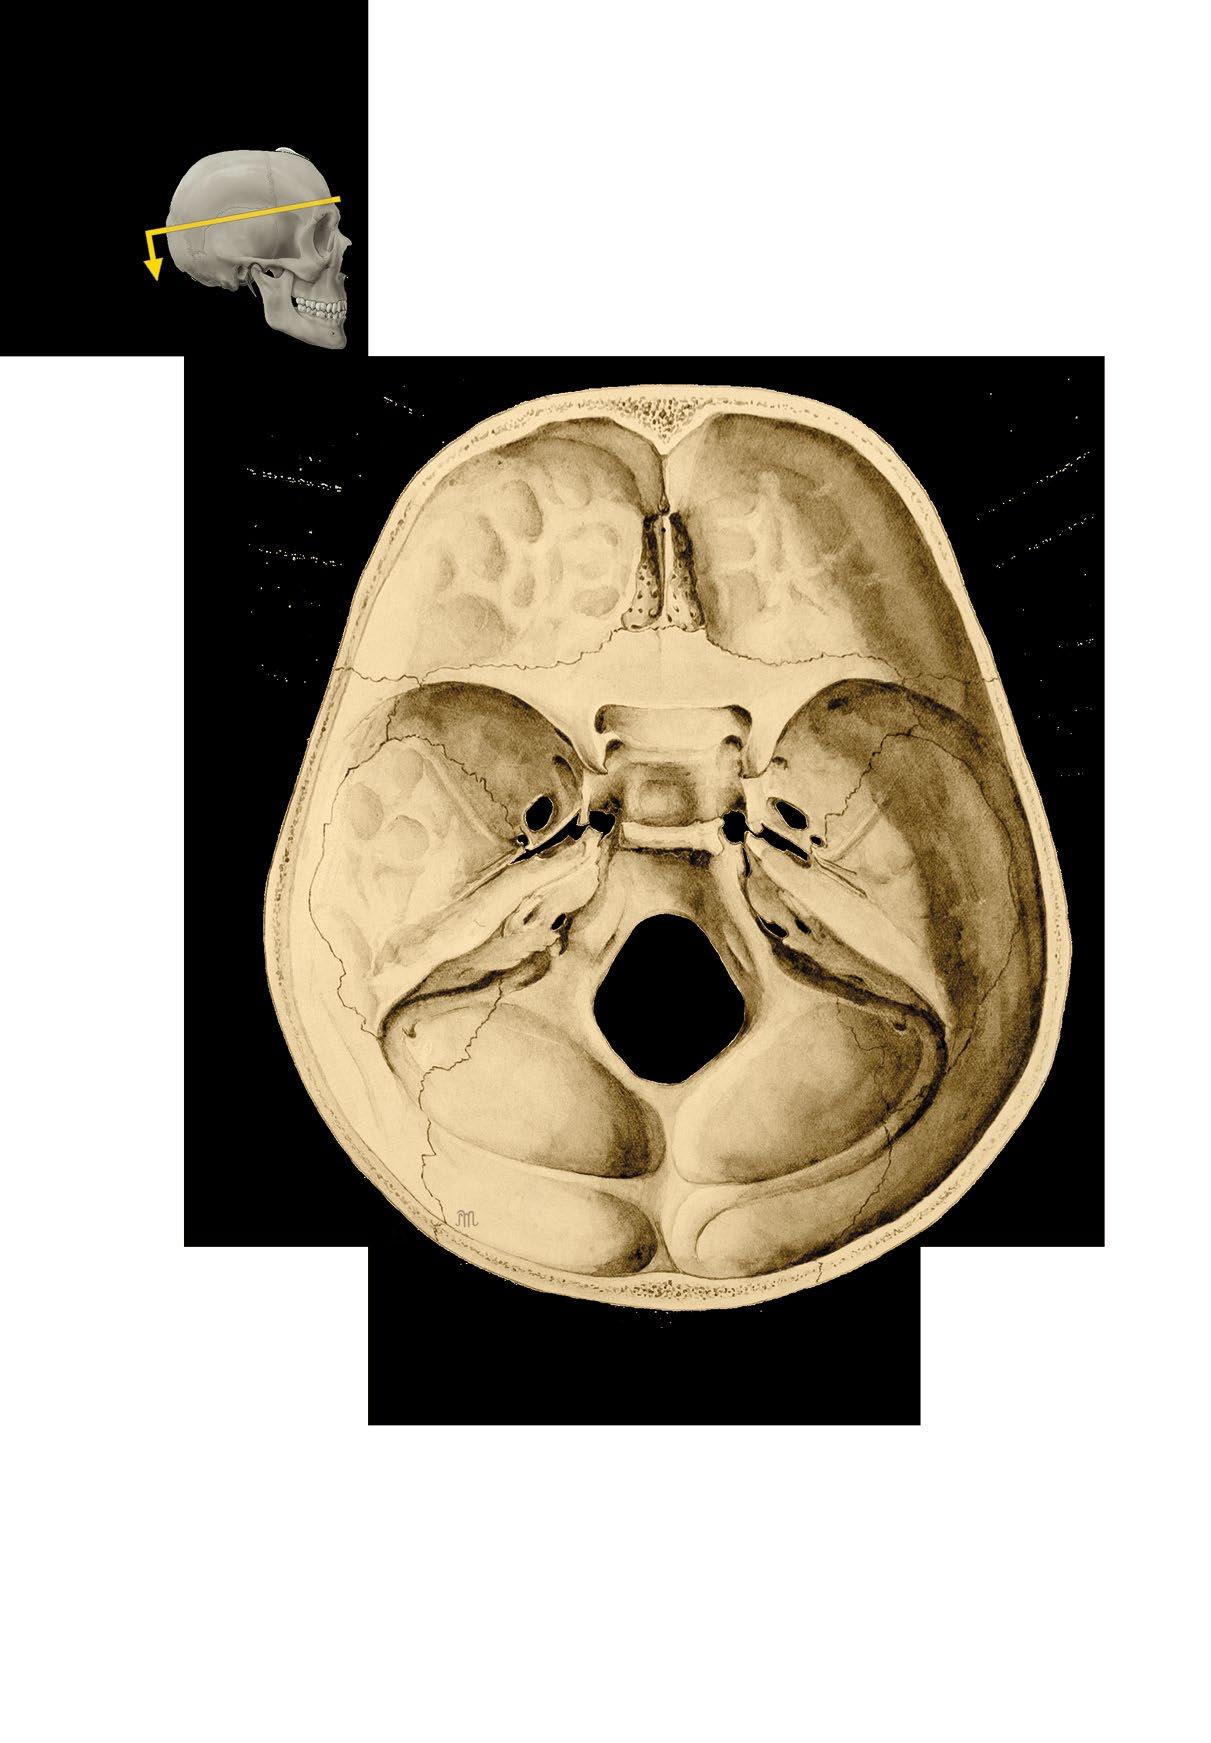

Basis cranii externa et interna

a zevní plocha base lební

b vnitřní plocha base lební

c členění vnitřní plochy base

External and internal base of the skull

a external surface

b internal surface

c cranial fossae